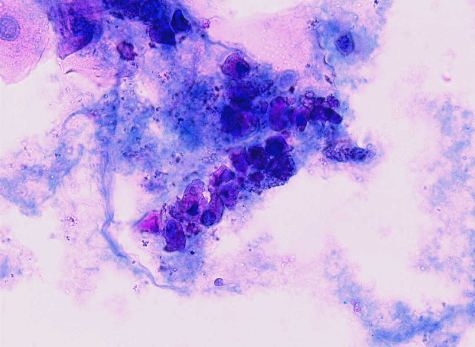

尿細管上皮細胞 角柱型

遠位〜集合管の尿細管上皮は立体感のある角柱型や角錐台型を示すものが多い。

立体型の角柱や角錐状を呈する

遠位尿細管や集合管を構成する細胞形態に酷似している